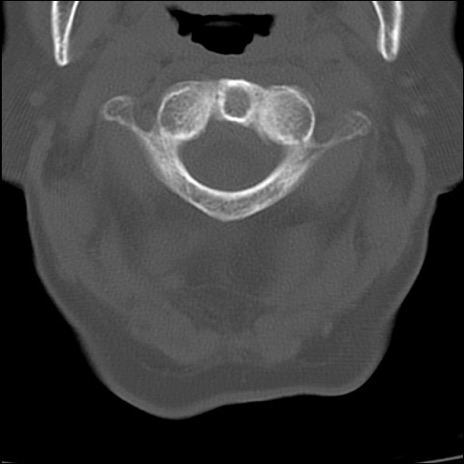

症例48 頚椎CT(横断像)

頚椎CT